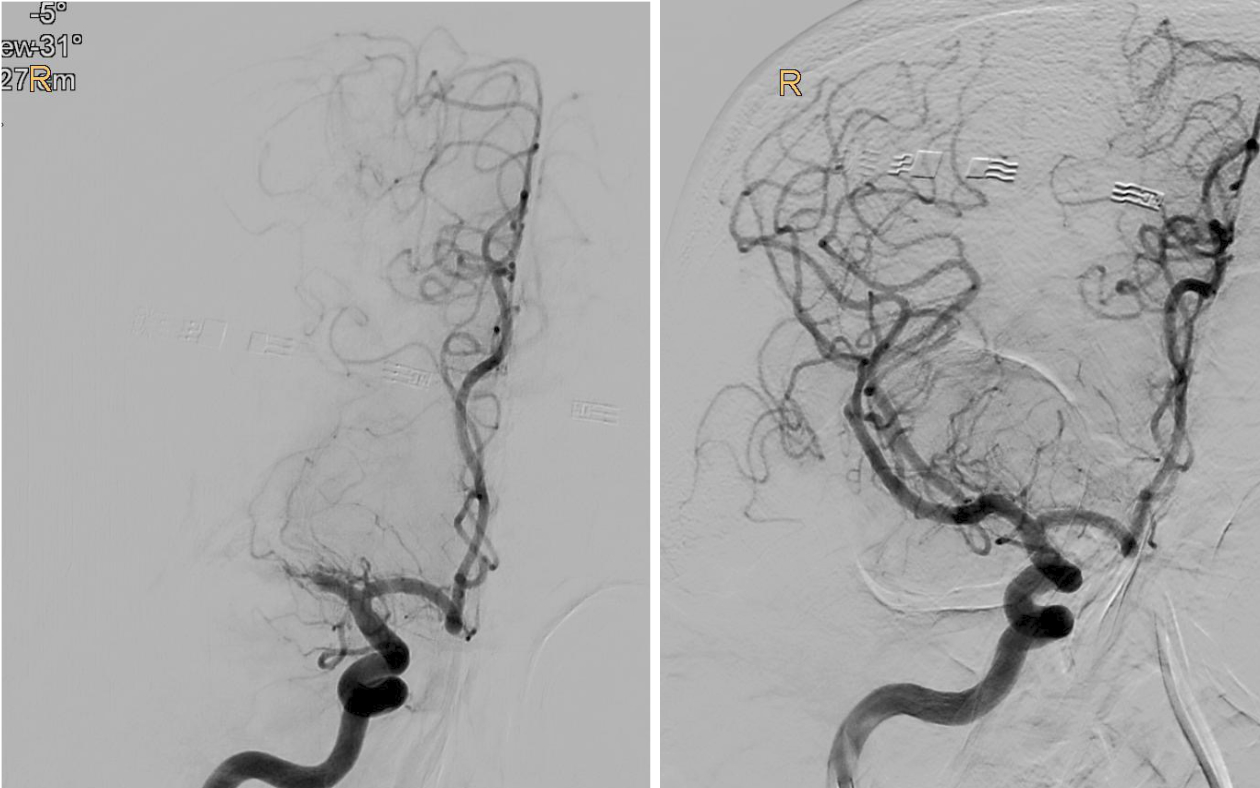

„Bei der Thrombektomie bringen wir mit einem Spezialkatheter von der Leiste ausgehend einen Stent an der Stelle des Gehirns ein, wo das Gerinnsel sitzt. Mit einer Saugvorrichtung wird das Blutgerinnsel dann zusammen mit dem Stent herausgezogen. Das Ganze passiert unter Röntgenkontrolle und bedarf viel Erfahrung“, erklärt Gizewski den sensiblen Vorgang. Vor 2015 wurde eine Thrombektomie standardmäßig meist nur durchgeführt, wenn eine Thrombolyse – medikamentöse Auflösung des Gerinnsels – bei den jeweiligen Patient:innen nicht durchgeführt werden konnte. Die großen Studien 2015 konnten zeigen, dass Patient:innen im frühen Stadium sehr von der Thrombektomie profitieren. Im Zuge der TENSION-Studie untersuchten die Expert:innen nun die Effektivität der Thrombektomie bei Schlaganfall-Patient:innen, deren Gehirn schon schwer geschädigt war.

„Bei einem Schlaganfall zählen einerseits Zeit und andererseits die noch verbliebene Sauerstoffversorgung des Gehirns, welche bei den Patient:innen unterschiedlich ausfällt. So genannte Kollaterale, Gefäß-Querverbindungen, können die Durchblutung noch einige Zeit aufrechterhalten. Je weniger solcher Kollateralen vorhanden sind, desto weniger Zeit hat man. Doch auch wenn schon Gewebe untergegangen ist, kann man noch etwas retten, wenn man thrombektomiert. Das konnten wir jetzt mit der TENSION-Studie zeigen“, berichtet Gizewski. Viele der Patient:innen könnten trotz der bedrohlichen Ausgangssituation jetzt wieder ein eigenständiges Leben führen. Nachdem sich der Erfolg der Katheter-Behandlung (insgesamt 125 Patient:innen) in der randomisierten Studie im Vergleich zur besten konservativen medizinischen Behandlung (128 Patient:innen) schnell gezeigt hatte, wurde die Studie frühzeitig beendet.